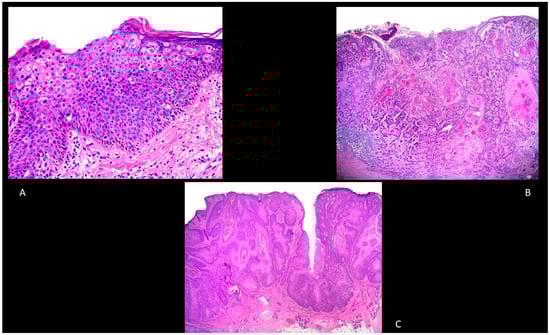

BD is an intraepidermal carcinoma with atypia of keratinocytes at all levels of the epidermis (in situ cSCC) [43]. The main histological features are parakeratosis, hyperkeratosis with an epidermis characterized by the presence of disordered maturation with atypical keratinocytes through all the epidermal layers, individual cell keratinization, pleomorphism of nuclei, atypical mitoses, and multinucleated tumor cells (Figure 2A). The basal layer is often not altered [43]. Keratinocytes can show pagetoid changes, while in other cases they show extensive clear cell changes. In the papillary dermis, a mixed inflammatory infiltrate characterized by lymphocytes and plasma cells can be often detected [43]. To exclude a melanoma, S100, Human Melanoma Black (HMB)-45 and Melan-A, and cytokeratin stains are usually employed [43].

Figure 2.

(A): Bowen’s disease. Hematoxylin and Eosin, 100× (B): Well-differentiated, invasive squamous cell carcinoma, hematoxylin and eosin, 20×. (C): Verrucous squamous cell carcinoma, hematoxylin and eosin, 20×.

Invasive cSCC is an epithelial malignancy characterized by atypical keratinocytes with a locally destructive growth and increased risk of metastatization. Histologically, it is mainly characterized by atypical and dyskeratotic keratinocytes with hyperchromatic and pleomorphic nuclei with mitoses (Figure 2B). Well-differentiated cSCCs typically have horn pearls and single cell keratinization, while poorly differentiated cSCCs usually show a lack of keratinization and many atypical mitoses. A mixed inflammatory infiltrate is usually present. Since the grade of differentiation is an important predictor, Broder’s staging is used to assess this parameter: grade I includes tumors composed of <25% undifferentiated cells, grade II lesions with <50% undifferentiated cells, grade III lesions with <75% undifferentiated cells, and grade IV lesions with >75% undifferentiated cells [40].

Verrucous cSCC (also known in genital areas as Buschke–Löwenstein tumor) is characterized by exophytic squamous proliferation with marked papillomatosis and low atypia, the presence of koilocyte-like changes, and a central collection of neutrophils (Figure 2C).

Adenosquamous cSCC is another type of cSCC characterized by a mixed glandular and squamous differentiation with an aggressive behavior (Figure 3A) [40].

Figure 3.

(A): Adenosquamous squamous cell carcinoma. Hematoxylin and eosin, 200×. (B): Perineural squamous cell carcinoma. Hematoxylin and eosin, 100×. (C): Papillary squamous cell carcinoma. Hematoxylin and eosin, 40×.